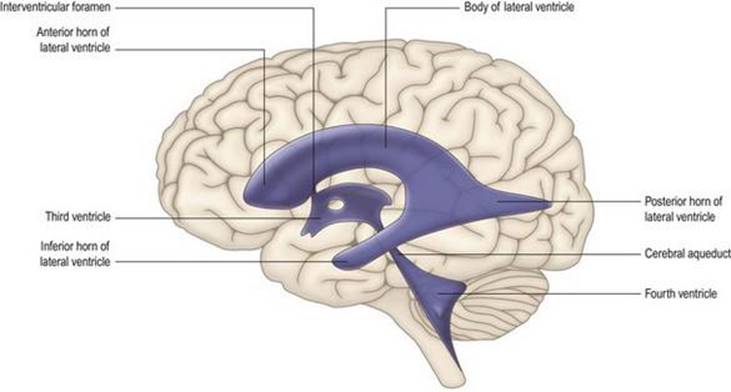

همانطور که مغز رشد میکند، حفره مرکزی آن نیز دستخوش تغییرات قابل توجهی در اندازه و شکل میشود و سیستمیاز حفرهها یا بطنها را تشکیل میدهد (شکل ۱.۱۰ و شکل ۱.۱۸ را ببینید) که حاوی مایع مغزی نخاعی (CSF) است.

سیستم بطنی

طرح بسیار ساده شده مغز پایه، که در بالا توضیح داده شد، طرح مفیدی است که در آن میتوان وضعیت کلی سیستم بطنی را در نظر گرفت (شکلهای ۱.۱۰، ۱.۱۲، ۱.۱۸). همانطور که کانال مرکزی نخاع به سمت ساقه مغز بالا میرود، به تدریج در جهت پشتی حرکت میکند و در نهایت باز میشود تا یک فرورفتگی کم عمق و لوزی شکل در سطح پشتی مدولا و پونز (قسمت مغزی عقبی ساقه مغز) ایجاد شود.) زیر مخچه. این بطن چهارم است.

شکل ۱.۱۸ سیستم بطنی مغزی.

شکل ۱.۱۸ سیستم بطنی مغزی.

در مرز منقاری حوضچهها، دیوارههای بطن چهارم به هم میرسند و بار دیگر یک لوله باریک به نام قنات مغزی را تشکیل میدهند. قنات مغزی به درون ماده ای از ساقه مغز که در طول مغز میانی در زیر کولیکولهای تحتانی و فوقانی قرار دارد فرو میرود. در محل اتصال مغز میانی و جلوی مغز، قنات به بطن سوم باز میشود، محفظهای شکافمانند، باریک از پهلو به پهلو، اما در ابعاد پشتی و شکمیو روسترو دمیگسترده است. دیوارههای جانبی بطن سوم توسط تالاموس و هیپوتالاموس دیانسفالون تشکیل شده است. در نزدیکی انتهای منقاری بطن سوم، یک روزنه کوچک، سوراخ بین بطنی (فورامن مونرو)، با یک محفظه وسیع، بطن جانبی ارتباط برقرار میکند.، در هر نیمکره مغزی. سیستم بطنی حاوی CSF است که توسط شبکه کوروئید ترشح میشود.

ساقه مغز

در طی رشد، نیمکره مغز در نتیجه مهاجرت رو به جلو لوب گیجگاهی، پیکربندی C شکل به خود میگیرد، به طوری که قطب تمپورال در مجاورت لوب فرونتال قرار میگیرد و توسط شکاف جانبی از آن جدا میشود. بنابراین، بطن جانبی در نیمکره نیز اساساً به شکل C است و «شاخهایی» به سمت لوبهای پیشانی، اکسیپیتال و گیجگاهی کشیده شده است (شکل ۱.۱۸).